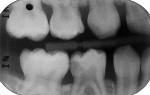

A boy aged 4 years and 11 months presented to the office with a large, deeply penetrating caries lesion on his mandibular right primary first molar (Figure 1). A bitewing radiograph suggested pulp exposure, but there were no clinical or radiographic signs or symptoms of pulp degeneration (Figure 2). The bitewing radiograph was also later used as a guide for crown size selection.